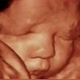

ÚNICA diag por imagem

#diagnostico #ultrassommorfologico #jundiaieregiao #diagnosticoporimagem #ultrassom3d sp